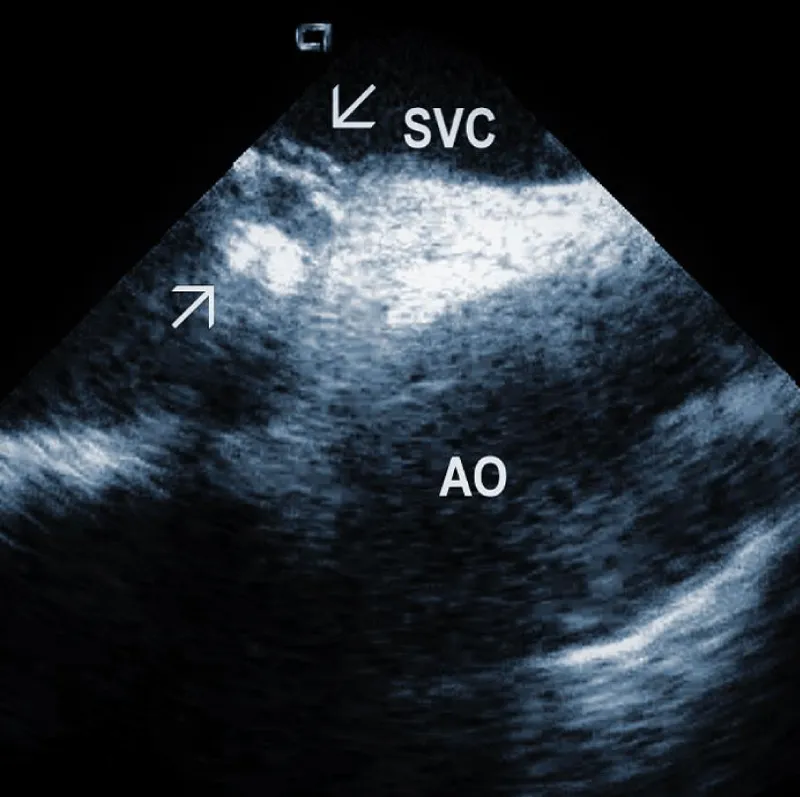

Areas of fibrous adherence: Areas of fibrous adherences or attachments (i.e., scar tissue) can be visualized as echo-dense structures along the lead course (Figure 3A). Multiple leads are usually attached by fibrous tissue together (Figure 3B). The location of fibrous adherence can be anywhere in the course of the lead [7,10]. In a study by Bongiorni, et al. [7], scar tissue was noted by ICE in the subclavian vein, innominate vein, and the right ventricle in about 80%, 68%, and 68% of cases, respectively. Sadek, et al. [10] described attachments less frequently – only in 18/50 pts (36%), predominantly intracardiac. Anecdotal cases were reported on specific locations of adhesions, such as a vulnerable “stalk” attaching the papillary muscle to the RV endocardium [18]. Notably, the fibrous attachment presence correlated with the extraction procedure’s difficulty. These patients were more likely to have a “complex” extraction procedure. Subjects who did not have evidence of lead attachment were less likely to require the advancement of the extraction sheaths past the superior vena cava and less likely to require advanced extraction tools such as snares.

Figure 3A: Fibrous adherences (arrow) attaching the lead within the superior vena cava (SVC). AO: Ascending aorta.